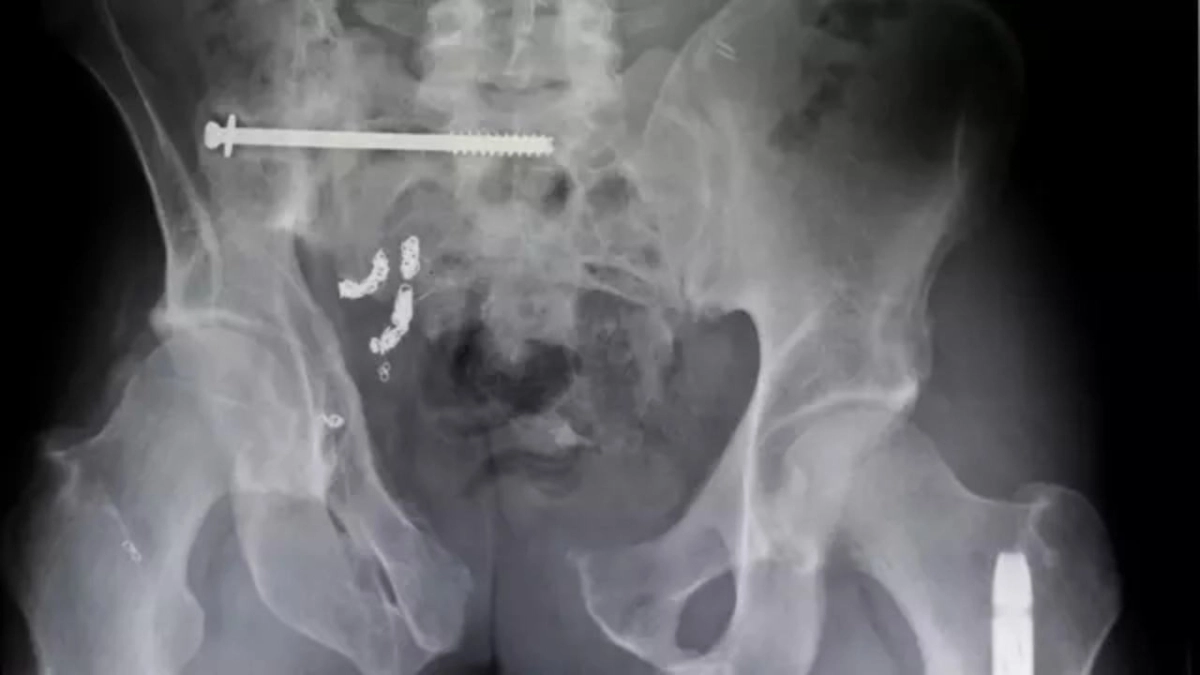

Βίδες και καρφιά